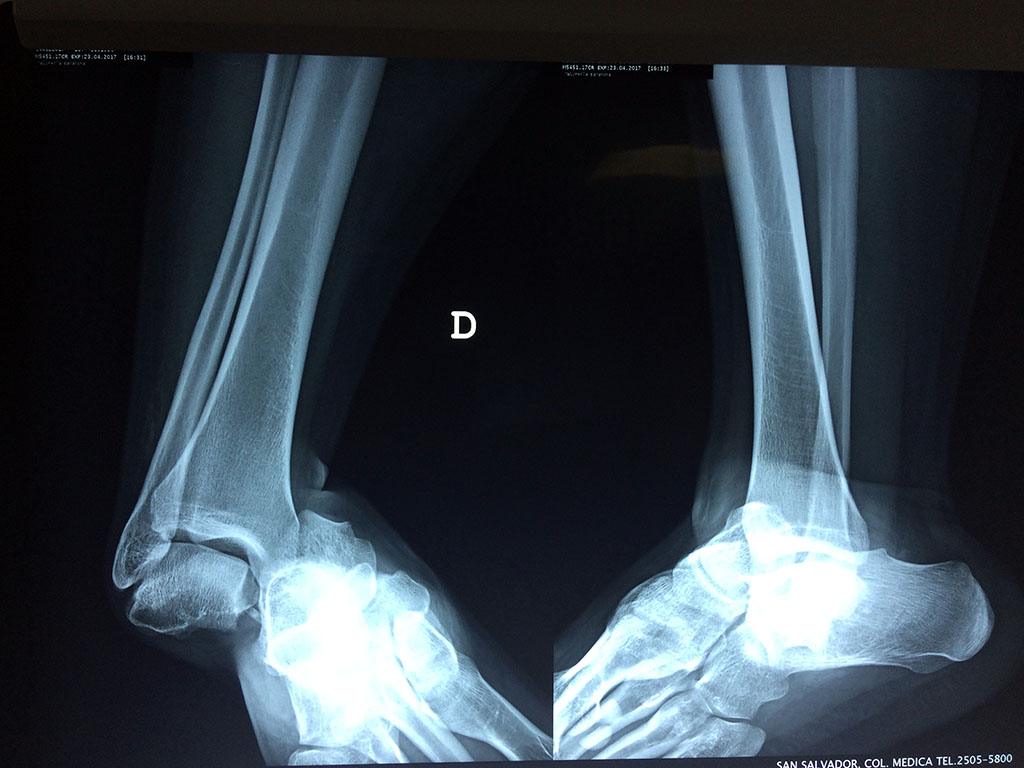

Una fractura de tobillo es la rotura de uno o más de los huesos del tobillo. Estas fracturas pueden ser:

Algunas fracturas de tobillo pueden requerir cirugía si:

- Los extremos de los huesos están desalineados entre sí (desplazados).

- La fractura se extiende hasta la articulación del tobillo (fractura intra-articular).

- Los tendones o ligamentos (tejidos que sujetan los músculos y los huesos entre sí) están rotos.

- El médico cree que sus huesos probablemente no sanen apropiadamente sin cirugía.

- El médico considera que la cirugía puede permitirle una recuperación más rápida y confiable.

- En los niños, la fractura involucra la parte del hueso del tobillo donde el hueso está creciendo.

Cuando se necesita cirugía, es probable que esta implique el uso de clavijas de metal, tornillos o placas para sostener los huesos en su lugar mientras la fractura se consolida. Los elementos de soporte pueden ser temporales o permanentes.